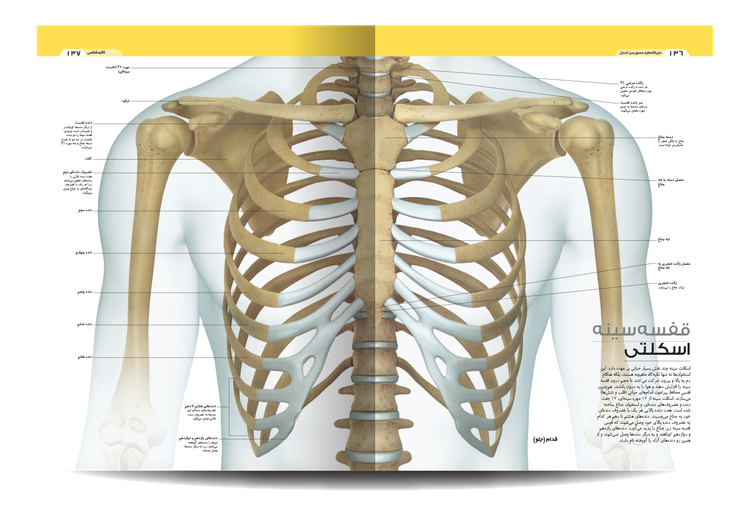

کتاب «دایره المعارف مصور بدن انسان» ، نگاهی دقیق به فرمها و عملکردهای بدن در فیزیولوژی و آناتومی ارائه میدهند و نحوه عملکرد بدن و سیستمها و تواناییهای شگفتانگیز آن را نشان میدهند.

آناتومی زیبای ما را ببینید و نحوه عملکرد اسکلت، ماهیچه ها و رباط ها را بخوانید. این ویرایش دوم شامل جزئیات بیشتری در مورد مفاصل دست و پا است. کتاب «دایره المعارف مصور بدن انسان» شما را از دوران نوزادی تا پیری می برد و نشان می دهد که بدن ما چگونه رشد می کند و تغییر می کند و چه چیزی ممکن است اشتباه باشد.

این راهنمای تصویری از تصاویر و نمودارهای قابل توجهی برای نگاه کردن به بدن پیچیده و شگفتانگیز ما استفاده میکند. این در قالبی ساده و با توضیحات ساده نوشته شده است تا بهترین نمای کلی از بسیاری از چیزهایی را که ما را انسان میسازند به شما ارائه دهد.